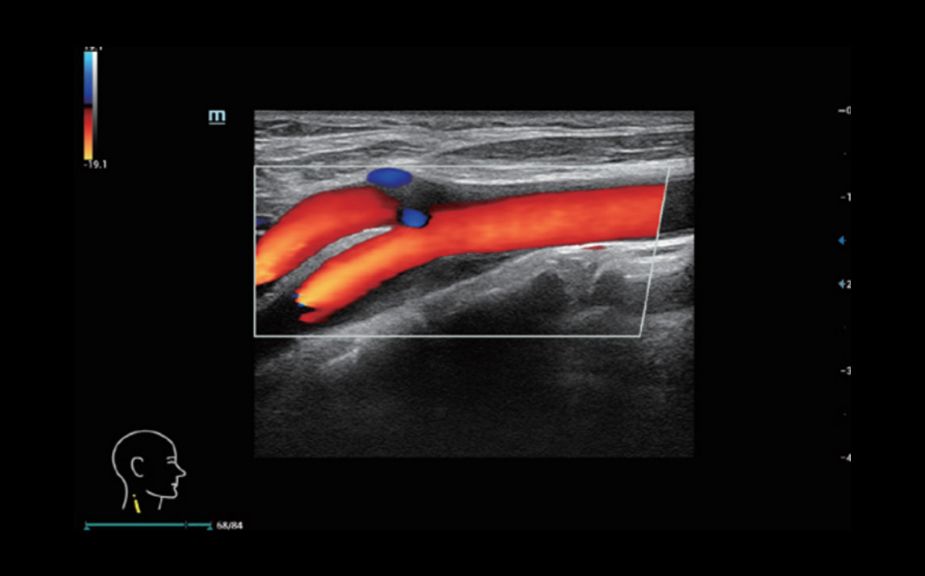

A Novel Approach of Vascular Hemodynamics: V Flow

Kolorowe wektory wskazuj? szybko?? i kierunek przep?ywu kom├│rek krwi. Dzi?ki wysokiej cz?stotliwo?ci od?wie?ania obrazu, V Flow zapewnia niezwykle ?yw?, dok?adn? i niezale?n? od k?ta nachylenia bramki dopplerowskiej wizualizacj? z?o?onych przep?yw├│w hemodynamicznych w naczyniach.

V Flow

A Novel Approach of Vascular Hemodynamics: V Flow

Kolorowe wektory wskazuj? szybko?? i kierunek przep?ywu kom├│rek krwi. Dzi?ki wysokiej cz?stotliwo?ci od?wie?ania obrazu, V Flow zapewnia niezwykle ?yw?, dok?adn? i niezale?n? od k?ta nachylenia bramki dopplerowskiej wizualizacj? z?o?onych przep?yw├│w hemodynamicznych w naczyniach.

V Flow